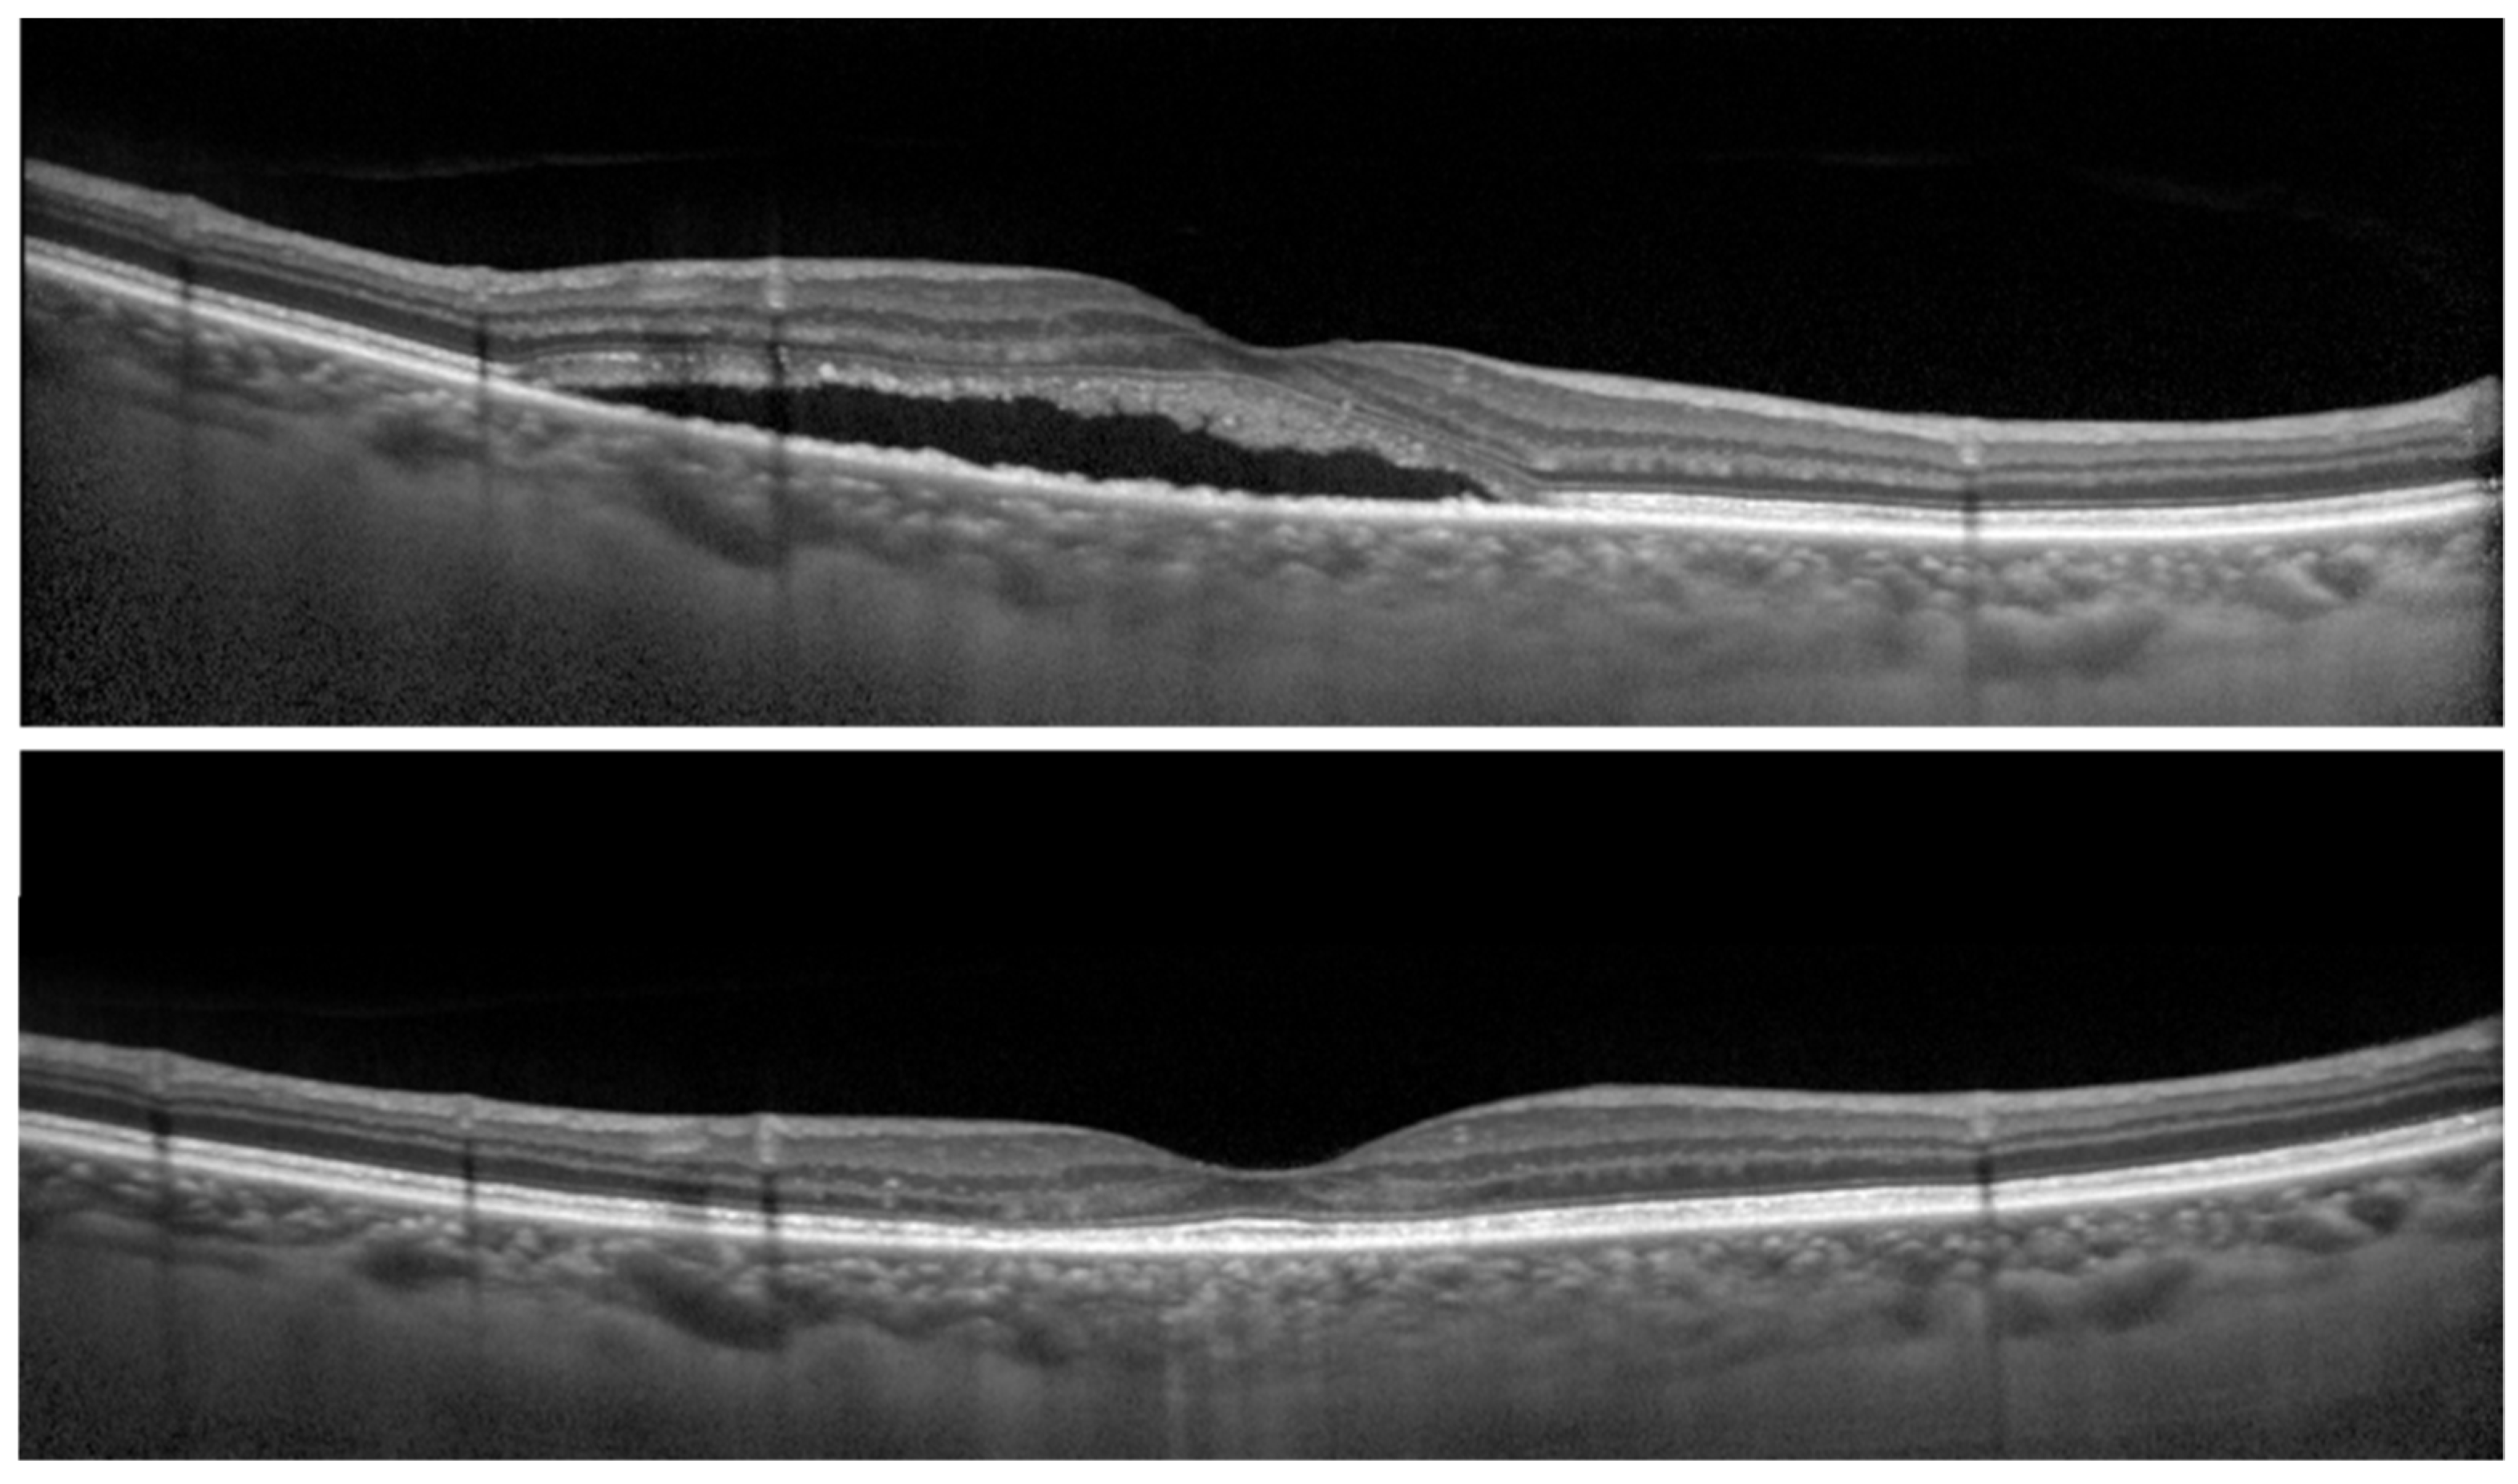

Figure 2. Optical coherence tomographic (OCT) images of the right eye of a 68-year-old man with central serous chorioretinopathy (CSC). (Top) Before reduced-fluence photodynamic therapy (RFPDT) and (Bottom) at 12 months after RFPDT. Complete resolution of SRD was observed after RFPDT. The 100% contrast visual acuity (decimal visual acuities) before and 12 months after RFPDT was 1.5, respectively. On the other hand, the 6% contrast visual acuity (decimal visual acuities) after RFPDT was 0.5. The symptom of duration was 11 months. The outer nuclear layer thicknesses before and after RFPDT were 69.0 and 92.0 µm, respectively.

Next, the association between 6% contrast visual acuity of affected eyes at post-RFPDT and clinical parameters including findings of OCT of affected eyes at pre- and post-RFPDT was investigated (Figure 2).

The 6% contrast visual acuities in affected eyes at post-RFPDT was significantly associated with symptom duration (p < 0.05) and the outer nuclear layer (ONL) thickness at pre-RFPDT showed a marginal significance (p = 0.052) (Table 4). Moreover, no significant association was observed between 6% contrast visual acuities at post-RFPDT and 100% contrast visual acuities at pre-RFPDT (Table 4).